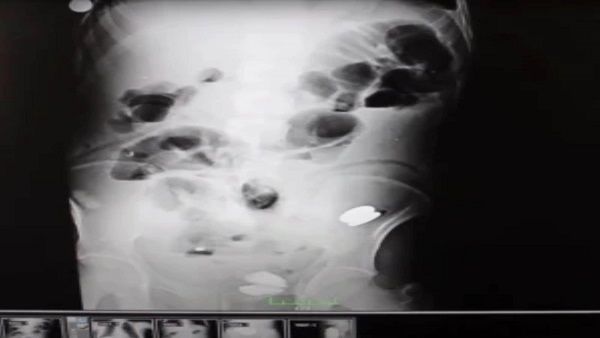

નવી દિલ્લીઃ ઘણીવાર બાળકો અજાણતામાં સિક્કા જેવી વસ્તુઓને ભૂલથી ગળી જાય છે પરંતુ પુખ્ત વયના લોકો પણ આવુ કરી શકે છે. તમને નવાઈ લાગશે પણ વાત સાચી છે. તુર્કીમાં ડોક્ટરોએ દર્દીના પેટમાંથી 250 ધાતુ, કાચ, સ્ક્રૂ, સિક્કા કાઢ્યા છે. જ્યારે ડોક્ટરોએ એ વ્યક્તિનો એક્સ-રે જોયો તો તેઓ દંગ રહી ગયા. તુર્કીના એપેક્યોલુમાં રહેતા એક વ્યક્તિએ પેટમાં દુખાવાની ફરિયાદ કર્યા બાદ ડૉક્ટરોનો સંપર્ક કર્યો. જ્યારે પ્રારંભિક ટેસ્ટમાં કંઈ ખાસ ન આવ્યુ ત્યારે ડૉક્ટરોએ એક્સ-રે કરાવવાનુ કહ્યુ.

બુરહાન મોટા ભાઈ સાથે ડેમિર હોસ્પિટલ પહોંચ્યો અને એક્સ-રે કરાવ્યો. જ્યારે તે રિપોર્ટ લઈને ડોક્ટર પાસે પહોંચ્યો તો ડોક્ટરો ચોંકી ગયા. અહેવાલ ચોંકાવનારો હતો. તે વ્યક્તિના પેટમાં 233 સિક્કા, બેટરી, ચુંબક, નખ, કાચના ટુકડા, પથ્થરો, ધાતુના સ્ક્રૂ જેવી વસ્તુઓ હતી. ડૉક્ટરોએ તેમની કારકિર્દીમાં આવો કિસ્સો પહેલીવાર જોયો હતો. રિપોર્ટ જોઈને ડોક્ટરો પણ સ્તબ્ધ થઈ ગયા.

ડૉક્ટરોએ જણાવ્યુ કે અત્યાર સુધીની કારકિર્દીમાં તેમણે આ પહેલા ક્યારેય આવી સર્જરી કરી નથી. બુરહાન ડેમિરના પેટમાં લગભગ 250 વસ્તુઓ હતી. જે તેની બીમારીનુ કારણ બની હતી. 35 વર્ષીય બુરહાનની સારવારમાં લાગેલી ટીમે અલ્ટ્રાસાઉન્ડ, એક્સ-રે સ્કેનિંગ, એન્ડોસ્કોપી જેવા ટેસ્ટ કરાવ્યા અને પછી સર્જરી કરી. બુરહાનના પેટમાંથી 250 વસ્તુઓ શોધીને તેને દૂર કરવી સરળ ન હતુ. ડૉકટરોએ કહ્યુ કે તેઓ પુખ્ત વયના લોકોમાં આવો કેસ ક્યારેય જોવા મળ્યો નથી.